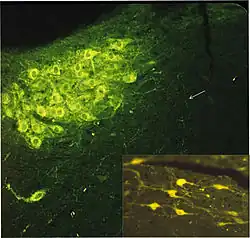

The next step led to the central nervous system. It was taken by Marthe Vogt, a refugee from Germany who at that time worked with John Henry Gaddum in the Institute of Pharmacology of the University of Edinburgh. "The presence of noradrenaline and adrenaline in the brain has been demonstrated by von Euler (1946) and Holtz (1950). These substances were supposed, undoubtedly correctly, to occur in the cerebral vasomotor nerves. The present work is concerned with the question whether these sympathomimetic amines, besides their role as transmitters at vasomotor endings, play a part in the function of the central nervous tissue itself. In this paper, these amines will be referred to as sympathin, since they were found invariably to occur together, with noradrenaline representing the major component, as is characteristic for the transmitter of the peripheral sympathetic system."[51] Vogt created a detailed map of noradrenaline in the dog brain. Its uneven distribution, not reflecting the distribution of vasomotor nerves, and its persistence after removal of the superior cervical ganglia made it "tempting to assign to the cerebral sympathin a transmitter role like that which we assign to the sympathin found in the sympathetic ganglia and their postganglionic fibers." Her assignment was confirmed, the finishing touch being the visualization of the noradrenaline as well as adrenaline and dopamine pathways in the central nervous system by Annica Dahlström and Kjell Fuxe with the formaldehyde fluorescence method developed by Nils-Åke Hillarp (1916–1965) and Bengt Falck (born 1927) in Sweden and by immunochemistry techniques.[52]